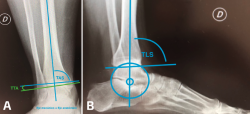

Figura 1.

En las radiografías simples con carga se evalúan las deformidades en los planos coronal y sagital. Las mediciones en el plano coronal son la superficie articular tibial distal (TAS-LDTA) con valores normales de 91 a 93° y el ángulo tibiotalar (TTA) con valores normales de 91,5 ± 1,2°. La inclinación talar (talar tilt) se calcula entre la diferencia de la TAS y el TTA. Se considera que un talar tilt con relevancia clínica es aquel mayor de 4°, considerando este valor como límite máximo de normalidad(6,15). La medición en el plano sagital es el ángulo tibial lateral o ángulo tibial anterior distal (TLS-ADTA), con valores normales de 81 ± 5°. En la clasificación de las malalineaciones con OA asimétricas de tobillo se hace más énfasis en la necesidad de corroborar que el centro de rotación del talo (considerado en el centro del proceso lateral del talo) esté en línea con el eje anatómico de la tibia en la radiografía lateral(7,8)(Figura 5).

Figura 5. A: superficie articular tibial (TAS) y ángulo tibiotalar (TTA); B: ángulo tibial lateral (TLS) y centralización de talo en eje anatómico.